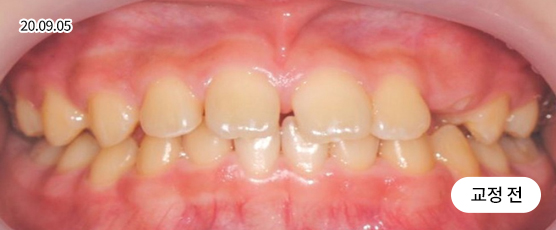

덧니교정 Solution

덧니는 악궁 크기, 얼굴형, 골격 등을 고려해 발치, 비발치를 현명하게 판단하여 치료합니다.

치아가 정렬될 공간을 확보하기 위해, 경우에 따라 소구치(작은 어금니)를 발치할 수 있습니다.

* 본 사진은 동일 조건에서 촬영되었으며, 환자 본인의 동의를 얻어 게재되었습니다.